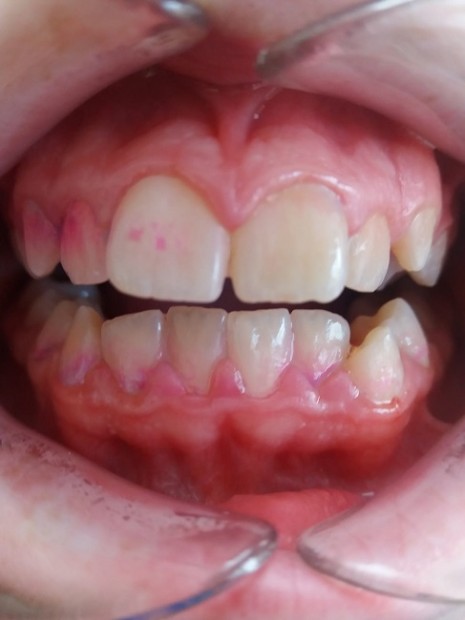

Fig. 1. Dental plaque

The patient can check the plaque at home or see his/ her dental hygienist. Dental hygienist does the tactile examination. Dental hygienist (DH) can feel slippery coating. When calcification has started, the plaque is slightly rough and can be taken away by an explorer passed over the surface. Plaque adheres to the explorer tip. When no plaque is visible it can be detected with disclosing agent, gel or tablet, it contains dye which turns violet colour to indicate plaque.

Fig. 2. Disclosing tablets